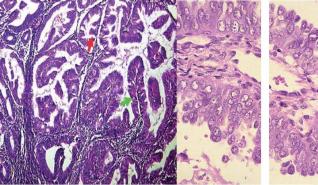

Das Endometriumkarzinom gilt als das "harmloseste" Genitalkarzinom der Frau, das meistens in einem frühen Stadium symptomatisch wird (Blutung) und deshalb eine relativ gute Prognose hat. Unter diesem Begriff verbirgt sich jedoch auch eine kleinere Gruppe von aggressiven Verlaufsformen mit schlechter Prognose, welche nach speziellen therapeutischen Konzepten verlangt.